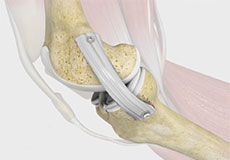

TLS Short Graft ACL Reconstruction

The TLS short graft ACL reconstruction is an advanced surgical technique performed to repair a torn ACL ligament in the knee. It involves the use of a tape locking screw (TLS) system that enhances the strength and mobility of the reconstructed ACL tendon, allowing the return to sports or an active lifestyle.